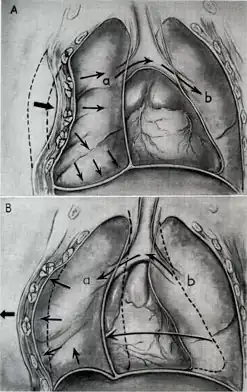

Blunt thoracic trauma

The term blunt thoracic trauma, or, more informally, blunt chest injury, encompasses a variety of injuries to the chest. Broadly, this also includes damage caused by direct blunt force (such as a fist or a bat in an assault), acceleration or deceleration (such as that from a rear-end automotive crash), shear force (a combination of acceleration and deceleration), compression (such as a heavy object falling on a person), and blasts (such as an explosion of some sort). Common signs and symptoms include something as simple as bruising, but occasionally as complicated as hypoxia, ventilation-perfusion mismatch, hypovolemia, and reduced cardiac output due to the way the thoracic organs may have been affected. Blunt thoracic trauma is not always visible from the outside and such internal injuries may not show signs or symptoms at the time the trauma initially occurs or even until hours after. A high degree of clinical suspicion may sometimes be required to identify such injuries, a CT scan may prove useful in such instances. Those experiencing more obvious complications from a blunt chest injury will likely undergo a focused assessment with sonography for trauma (FAST) which can reliably detect a significant amount of blood around the heart or in the lung by using a special machine that visualizes sound waves sent through the body. Only 10–15% of thoracic traumas require surgery, but they can have serious impacts on the heart, lungs, and great vessels.[12]

The most immediate life-threatening injuries that may occur include tension pneumothorax, open pneumothorax, hemothorax, flail chest, cardiac tamponade, and airway obstruction/rupture.[12]

The injuries may necessitate a procedure, most commonly the insertion of an intercostal drain, or chest tube. This tube is typically installed because it helps restore a certain balance in pressures (usually due to misplaced air or surrounding blood) that are impeding the lungs' ability to inflate and thus exchange vital gases that allow the body to function.[13] A less common procedure that may be employed is a pericardiocentesis, which, by removing blood surrounding the heart, permits the heart to regain some ability to appropriately pump blood.[14][15] In certain dire circumstances an emergent thoracotomy may be employed.[16]

Treatment of blunt thoracic trauma

Nine out of ten patients with thoracic trauma can be treated effectively without a surgical operation.[37] If surgery is indicated, there are numerous options available. A comprehensive discussion between the patient and the surgeon will take place to carefully evaluate the best approach, tailored to the patient's specific condition and injury. Conservative measures such as maintaining a clear and open airway, oxygen support, tube thoracostomy, and volume resuscitation are often given to manage blunt thoracic trauma.[37] Oftentimes, pain control is the most basic and effective treatment approach because the presence of severe pain may lead to impairment of proper breathing, further exacerbating impaired lungs.[37] Pain management in thoracic trauma patients improves the ability to breathe properly on their own, encourages the excretion of pulmonary secretions, and decreases the aggravation of inflammation and low oxygen levels in the blood.[37] Nonsteroidal anti-inflammatory drugs, opioids, or regional pain management methods, such as local anesthetic, can be used for pain control.[37]